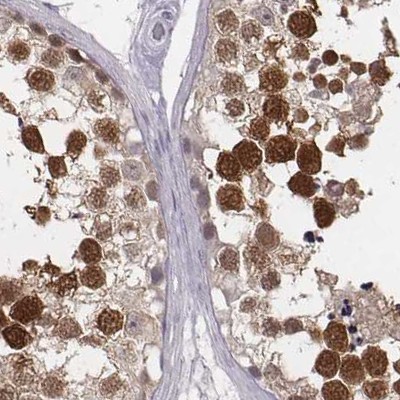

Immunohistochemistry analysis in human testis and endometrium tissues using Anti-PBK antibody. Corresponding PBK RNA-seq data are presented for the same tissues.